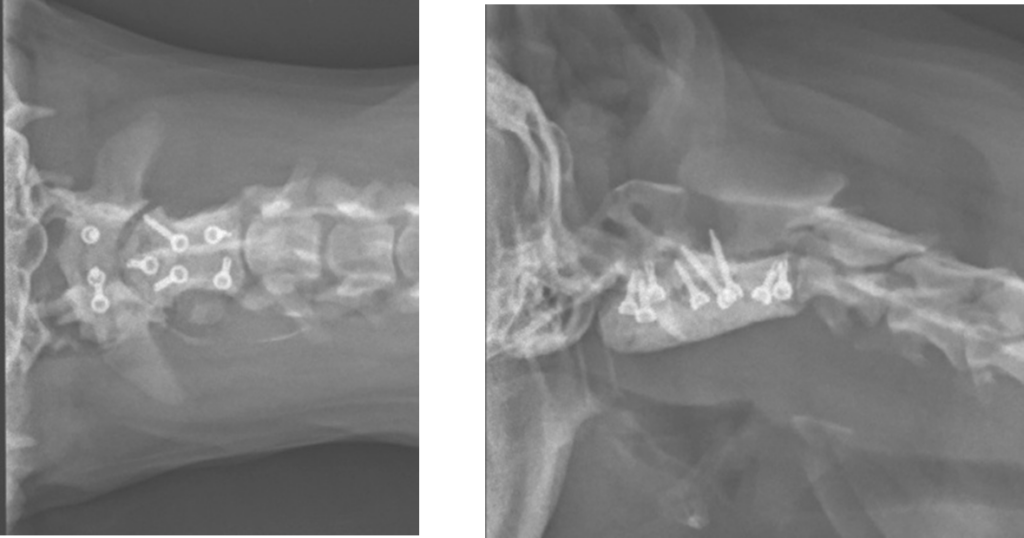

中等度〜重度の症状がある場合や、内科治療で改善しない場合に推奨される、最も根本的な治療法です。手術では、ずれてしまった環椎と軸椎を正常な位置に戻し、特殊なネジやプレート、医療用セメントなどを使って固定します。これにより、脊髄への圧迫を取り除き、首を安定させることができます。手術は非常に繊細で高度な技術を要しますが、成功すれば劇的に症状が改善し、良好な生活を送れるようになる可能性が高まります。

確定診断をするために、MRI検査が可能な専門施設をご紹介しました。MRI検査の結果、環軸亜脱臼と診断され、1週間後に専門施設にて手術が行われました。

セカンドオピニオン来院時にはCK(筋肉や心臓、脳神経に多く含まれる酵素で、これらの組織がダメージを受けると血液中に流出するため、その値を測定する血液検査です。)の値が1770と高値でしたが、オペ後は正常値に戻りました。

症状から環軸亜脱臼を疑い、適切にレントゲン検査撮影をし、MRI検査を紹介したことで確定診断及び手術に繋がった症例でした。